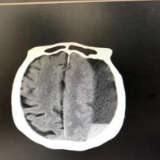

在长沙市第三医院完善相关检查后,郭娭毑被诊断为左侧额颞顶枕部慢性硬膜下血肿。血肿量约120毫升,若不及时进行手术引流,老人随时可能因脑疝形成导致临床死亡。

神经外科团队在对郭娭毑的情况进行了全面评估后,制定了个性化微创手术治疗的方案——左侧额颞顶枕部慢性硬膜下血肿钻孔引流术。

手术过程顺利,仅耗时约半小时。术后引流管引出血性液体约150毫升,郭娭毑意识当即恢复清醒;术后第一天,老人右侧肢体功能立即得到恢复,还能自行拿着手机同家人视频报平安!